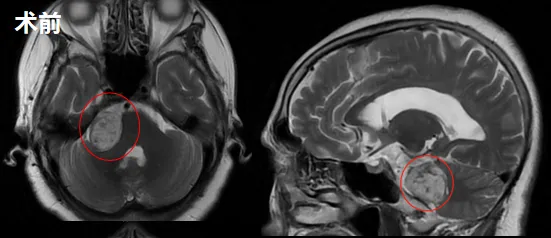

70岁患者齐奶奶2018年出现右耳听力下降,初被视为正常衰老现象。2020年症状加重,出现行走偏斜、下肢无力、跌倒及大小便失禁。2021年MRI检查确诊为右侧听神经瘤(20mm×15mm×19mm)合并脑积水。经多学科评估,患者先接受脑积水引流术缓解症状。2022年10月复查显示肿瘤增大至3厘米,遂行手术全切。术后患者恢复良好,一年后生活完全恢复正常。